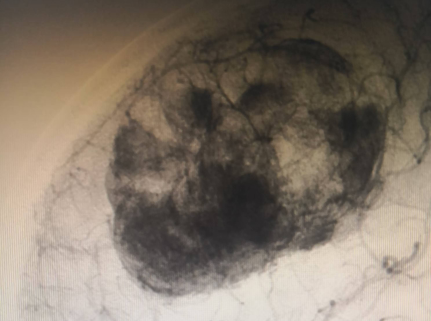

神经外科血管介入组曲友直副教授、崔刚副教授和高攀主治医师对肿瘤进行了瘤栓塞治疗,有效减少了肿瘤的血供,为后续的手术切除降低了风险。栓塞治疗后,神经外科王睿智副主任、高李贵副教授和董全主治医师在麻醉科、心内科、输血科等科室的全力配合下,凭借精湛的医术和丰富的临床经验,成功为患者切除了病变。手术过程中,麻醉科吕建瑞主任团队全程监控患者的生命体征,确保麻醉安全;心内科团队随时准备应对可能出现的心脏问题;输血科团队则确保充足的血液供应,以备不时之需。多学科的通力合作,为手术的成功提供了坚实的保障。